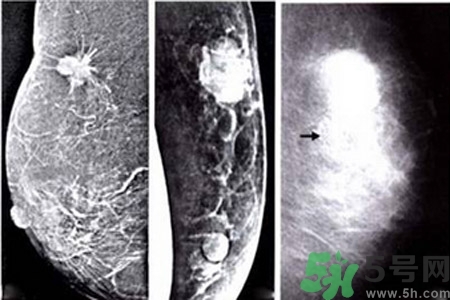

乳腺增生鈣化是乳腺癌常見(jiàn)的影像學(xué)表現(xiàn)之一。某些特異形態(tài)的乳腺增生鈣化是乳腺癌的危險(xiǎn)因素,統(tǒng)計(jì)資料表明65%的乳腺癌有鈣化,其中70%為惡性鈣化。

早期乳腺癌唯一的X線征象

成簇樣微小鈣化常是早期乳腺癌唯一的X線征象。根據(jù)微小鈣化形態(tài)、大小、數(shù)量和密集度等表現(xiàn)可反映病變性質(zhì)和范圍。微小鈣化點(diǎn)可位于腫塊內(nèi)或周圍,總數(shù)目6~15枚,密度不均,大小不等。

乳腺X線檢查可提高隱匿癌、微小癌(直徑小于10mm)和早期癌的診斷率。直徑小于10mm腫塊定性困難,但細(xì)沙型鈣化常是惡性病變的警報(bào);若同時(shí)出現(xiàn)周圍結(jié)構(gòu)紊亂,雙側(cè)不對(duì)稱,血管影增粗等征象則惡性病變可能性更大。

良性惡性乳腺增生鈣化的差異

與良性乳腺增生鈣化相比,惡性乳腺增生鈣化群平均密度較低,密度及大小對(duì)乳腺疾病良惡性鑒別價(jià)值較大。乳腺X線片中微小鈣化分布似乎無(wú)規(guī)律可循,但病理發(fā)現(xiàn)癌腫發(fā)生于末梢導(dǎo)管時(shí),鈣化可位于大片壞死組織中或癌細(xì)胞間,亦可存在于所屬上級(jí)導(dǎo)管內(nèi)或?qū)Ч芊植嫣幓蛳噜徬倥萸粌?nèi)。